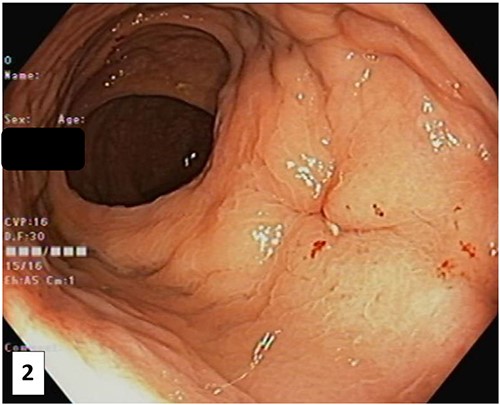

The patient was referred to a colorectal surgeon who performed a repeat colonoscopy and examination of the anorectum under anaesthesia. These showed a healing sinus at the anterior low rectum (Fig. 2), coinciding with the region of interest described in the MRI. At this point, the patient was asymptomatic.

Photograph of the anterior rectal wall taken at colonoscopy after the SpaceOAR Vue was noted to be missing. This lesion, likely a healing sinus, corresponds to the location of the abnormality of the pelvic MRI.